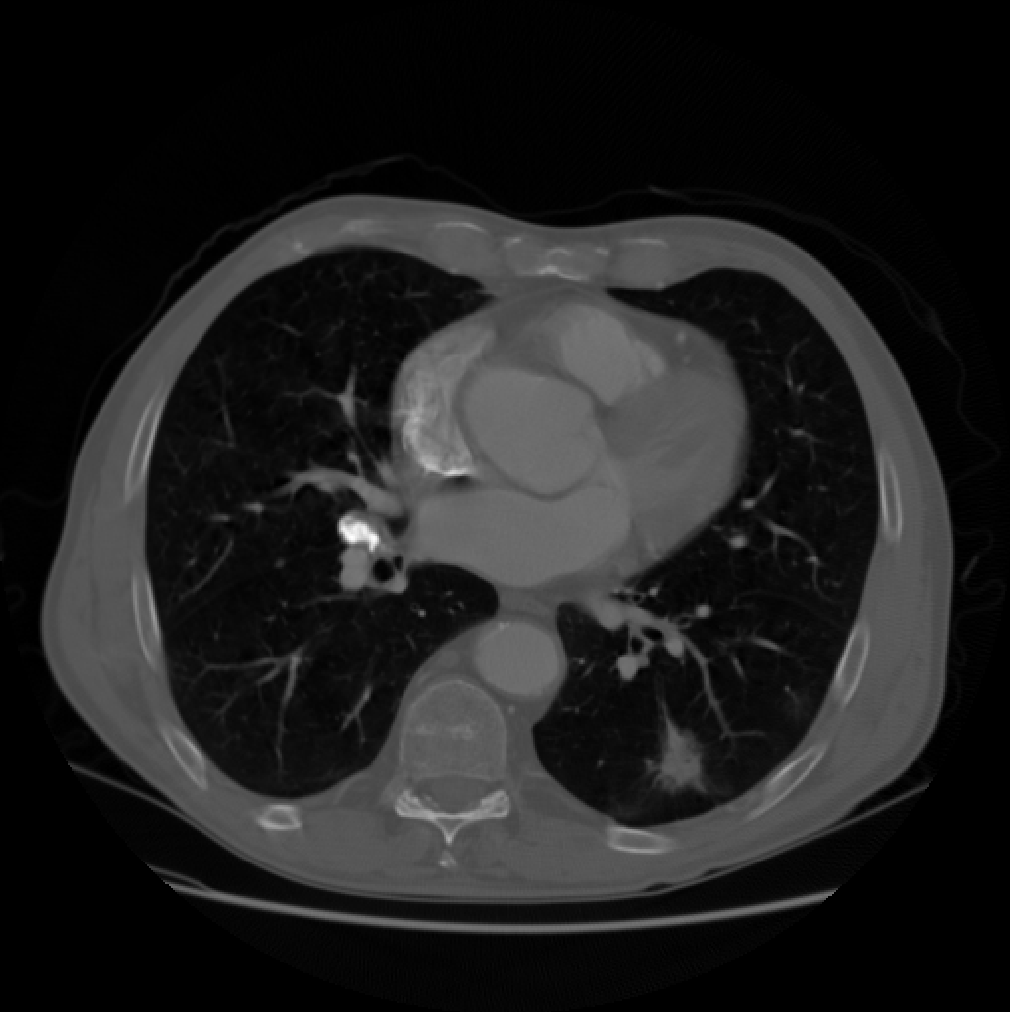

We compare the computation time and SNR of back projection among oblique method, orthogonal method under band limited assumption and box spline methods. We throughly test the performance of oblique method, box spline methods and blurred box spline method (box spline method with detector blur effect). Three images are used in our experiments, the first one consists of randomly placed ellipses, the second one is Forbild head phantom, and the last one is a real CT image from LIDC-IDRI dataset [13] (Fig.2). In our experiments, we fix the sampling steps to be equal in all dimensions, 𝚲x=λxI2subscript𝚲𝑥subscript𝜆𝑥subscript𝐼2\boldsymbol{\Lambda}_{x}={\lambda}_{x}I_{2} and λy=nλxsubscript𝜆𝑦𝑛subscript𝜆𝑥\lambda_{y}=n\lambda_{x}, where n𝑛n is the downsampling rate. The number of views is set to 180180180. Signal to noise ratio (SNR) in dB and structural similarity index (SSIM) are measured for all the methods. All computations were done on one PC (Windows 10 with a 3.7GHz 6-Core Intel Core i7-8700K processors and 32GB of RAM) using Matlab.

Refer to caption

(a)

(b)

(c)

Fig. 2: The three images used in our experiments. (a) Spots. (b) Forbild phantom. (c) A real CT image.